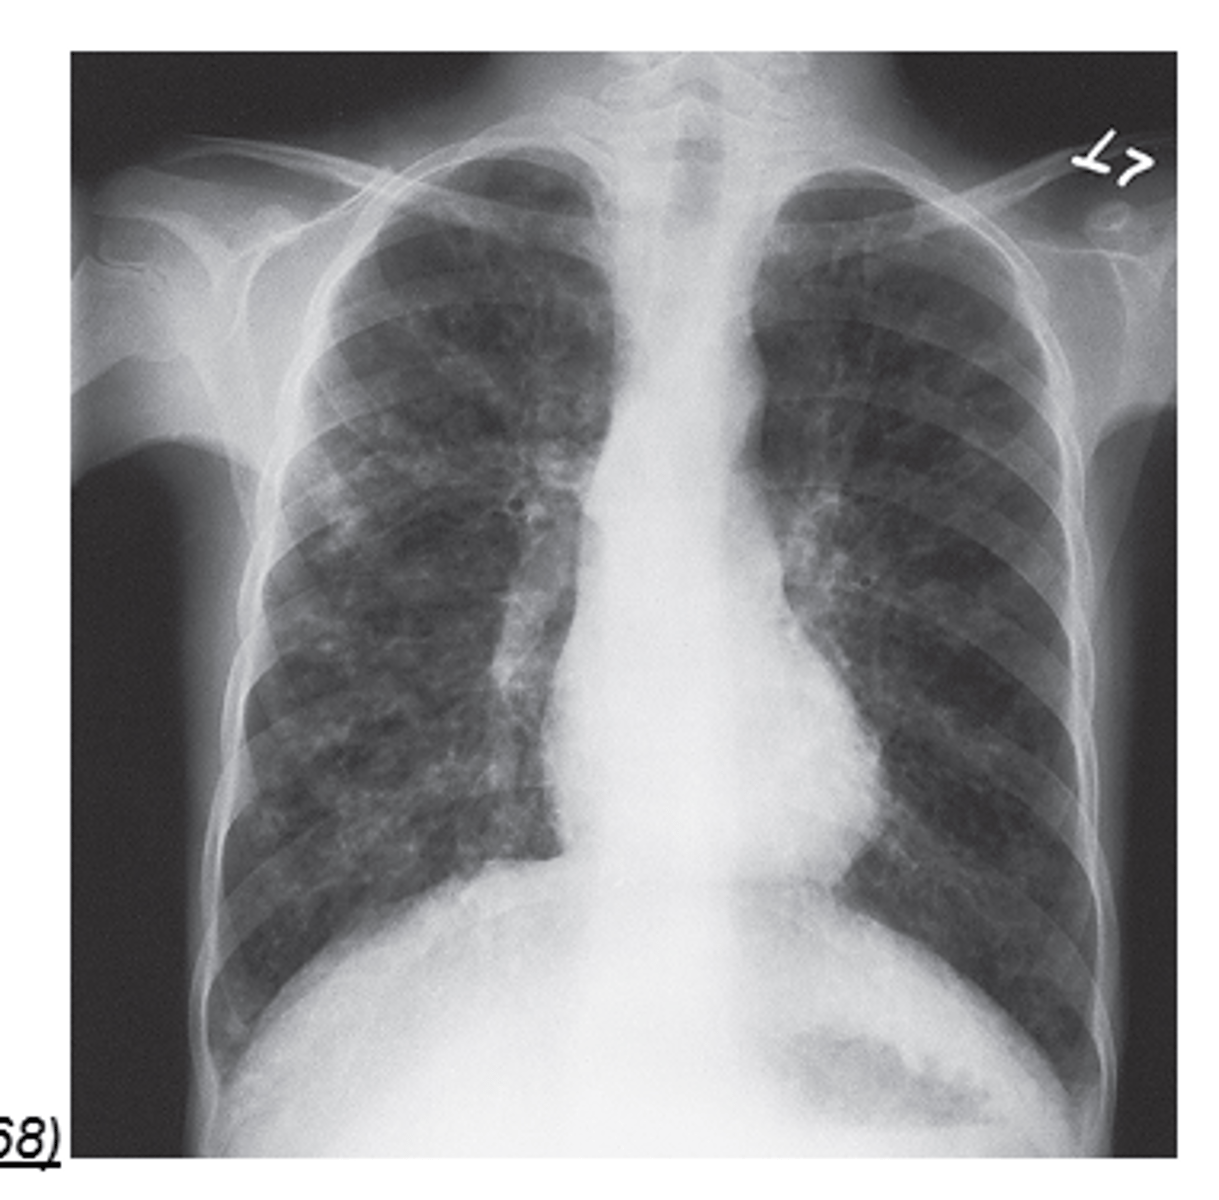

Cystic Fibrosis definition

A disorder resulting from a genetic defect transmitted as an autosomal recessive gene that affects the function of exocrine glands

Modality for Cystic Fibrosis

Radiography

most common lethal genetic disease in white children

Cystic Fibrosis